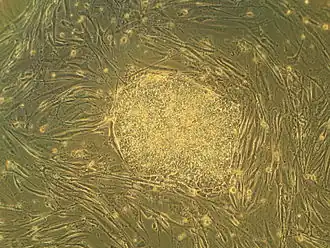

Algunas de las aproximaciones biomédicas dentro del campo de la medicina regenerativa, pueden implicar el uso de células raíz, también denominadas células madre.[8] Los ejemplos incluyen la inyección de células de raíz o células progenitoras obtenidas a través de diferenciación dirigida (terapias celulares); la inducción de regeneración por moléculas activas biológicamente, administradas solas o como secreción por células infundidas (terapia de inmunomodulación); y trasplante de tejidos y órganos crecidos en vitro (ingeniería de tejidos).[9][10]